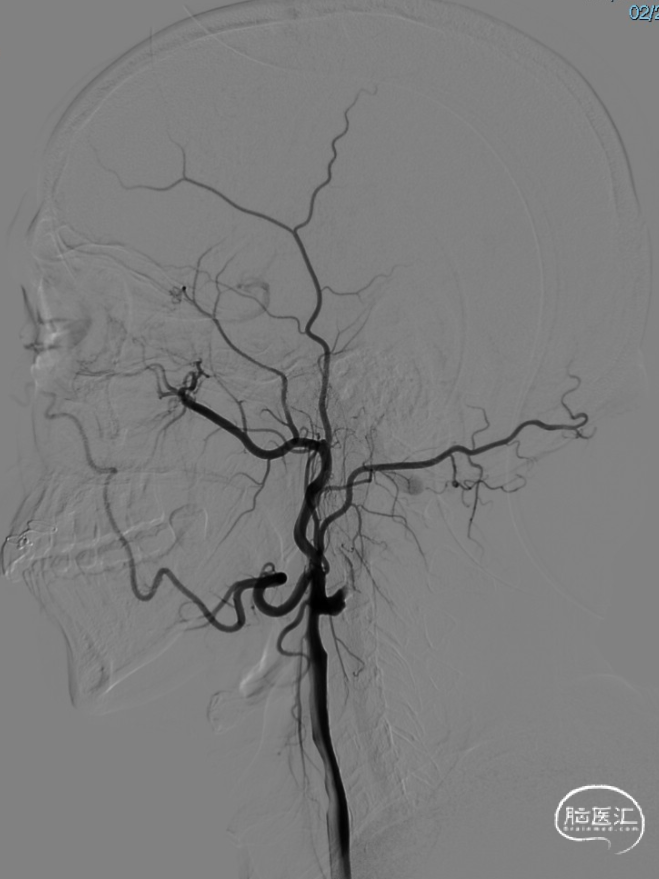

术后即刻影像。

支架植入后造影提示残余狭窄约10%。术中患者生命体征稳定,术后患者恢复良好出院,继续抗血小板聚集及他汀类药物治疗。